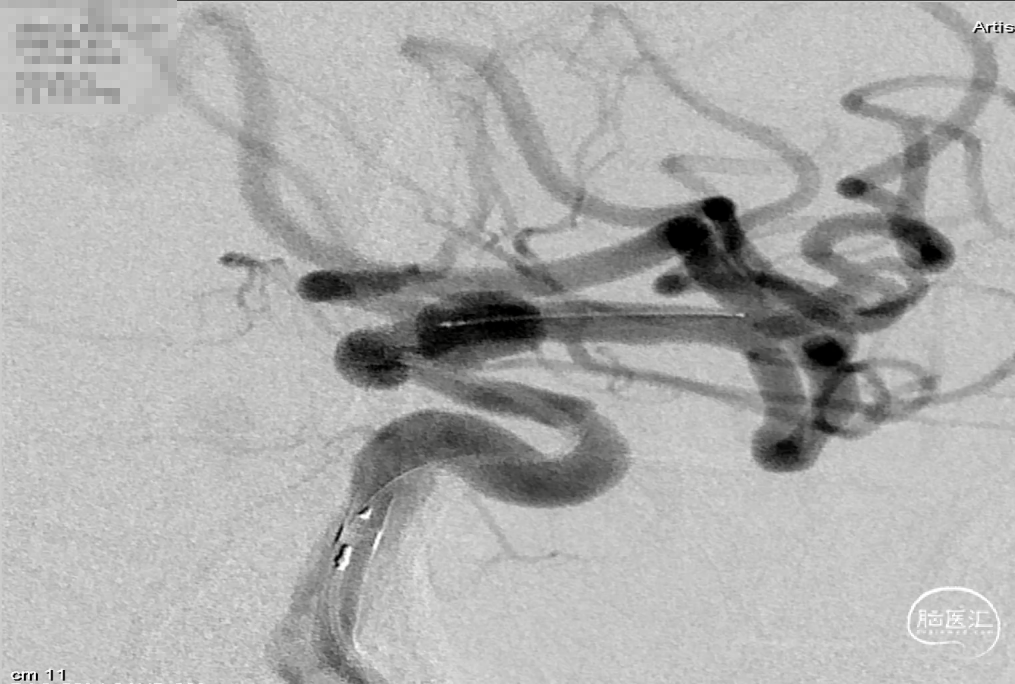

工作位透视下观察可见支架打开良好,复查造影可见支架打开良好,动脉瘤内可见造影剂滞留。

术后工作位造影

术后标准正位造影